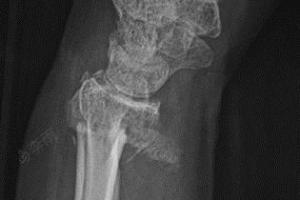

右手尺桡骨双colles骨折

右手桡骨远端及尺骨茎突骨折